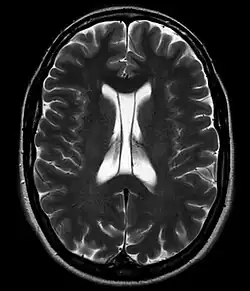

Cavum septi pellucidi / Cavum vergae in der Kernspintomographie, T2 axial

Als Cavum septi pellucidi (auch Septum-pellucidum-Zyste, Pseudoventrikel, fünfter Ventrikel, Duncans Ventrikel, Sylvischer Ventrikel, Vieussens’ Ventrikel, Wenzels Ventrikel und weitere) bezeichnet man den Hohlraum zwischen den Blättern des Septum pellucidum zwischen den Vorderhörnern der Seitenventrikel des Gehirns. Wenn eine Ausdehnung nach dorsal hinter das Foramen Monroi vorliegt, spricht man von einem Cavum vergae, wobei es sich nicht um eine andere anatomische Struktur handelt.

Das Cavum septi pellucidi ist eine normale anatomische Struktur in der Entwicklung des Feten, die beim Erwachsenen in der Regel zurückgebildet bzw. obliteriert ist. Man findet das Cavum septi pellucidi noch bei praktisch allen Frühgeborenen, bei 85 % normaler Neugeborener und in 1 bis 20 % noch bei Erwachsenen. Ein Cavum vergae zeigt sich bis zum 6. Monat ebenfalls bei 100 % der Feten und bei 30 % der normalen Neugeborenen. Bei Erwachsenen wird eine Häufigkeit von weniger als 1 % angegeben.

Der Hohlraum beinhaltet in der Regel normalen Liquor. Eine Kommunikation mit den anderen Liquorräumen kann, muss aber nicht vorhanden sein. Als Zufallsbefund beim Erwachsenen in der Computertomographie oder Kernspintomographie gefunden, ist das Cavum meist nur wenige Millimeter groß. Auch größere Befunde machen selten Probleme. In Einzelfällen kommt es zu einer Kompression des Foramen Monroi mit Ausbildung eines Hydrozephalus. In diesen Fällen ist eine neurochirurgische Behandlung zur Dekompression notwendig.